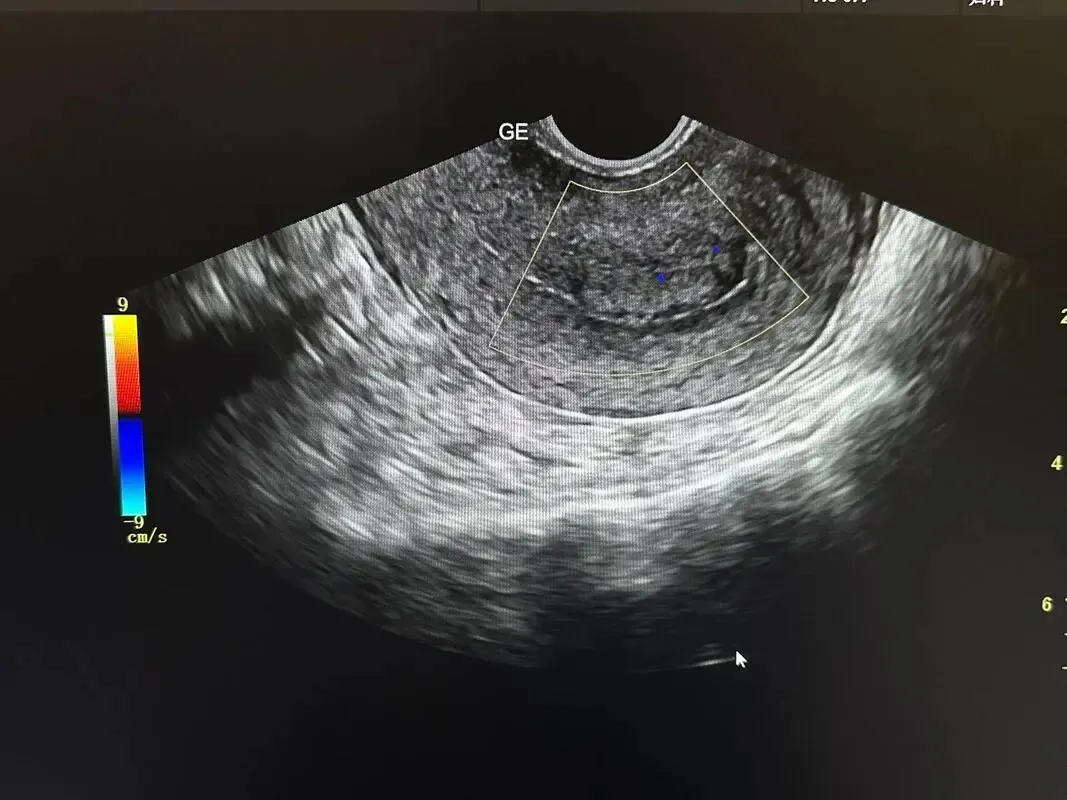

倒逼基层医疗服务能力提升。“工欲善其事,必先利其器。”更先进的超声设备,意味着更清晰的图像、更精准的诊断、更丰富的功能,如弹性成像、造影增强等。这将直接提升县级医院和乡镇卫生院的影像诊断水平,让更多疾病能在县域内得到准确诊断,实现“大病不出县”的目标。